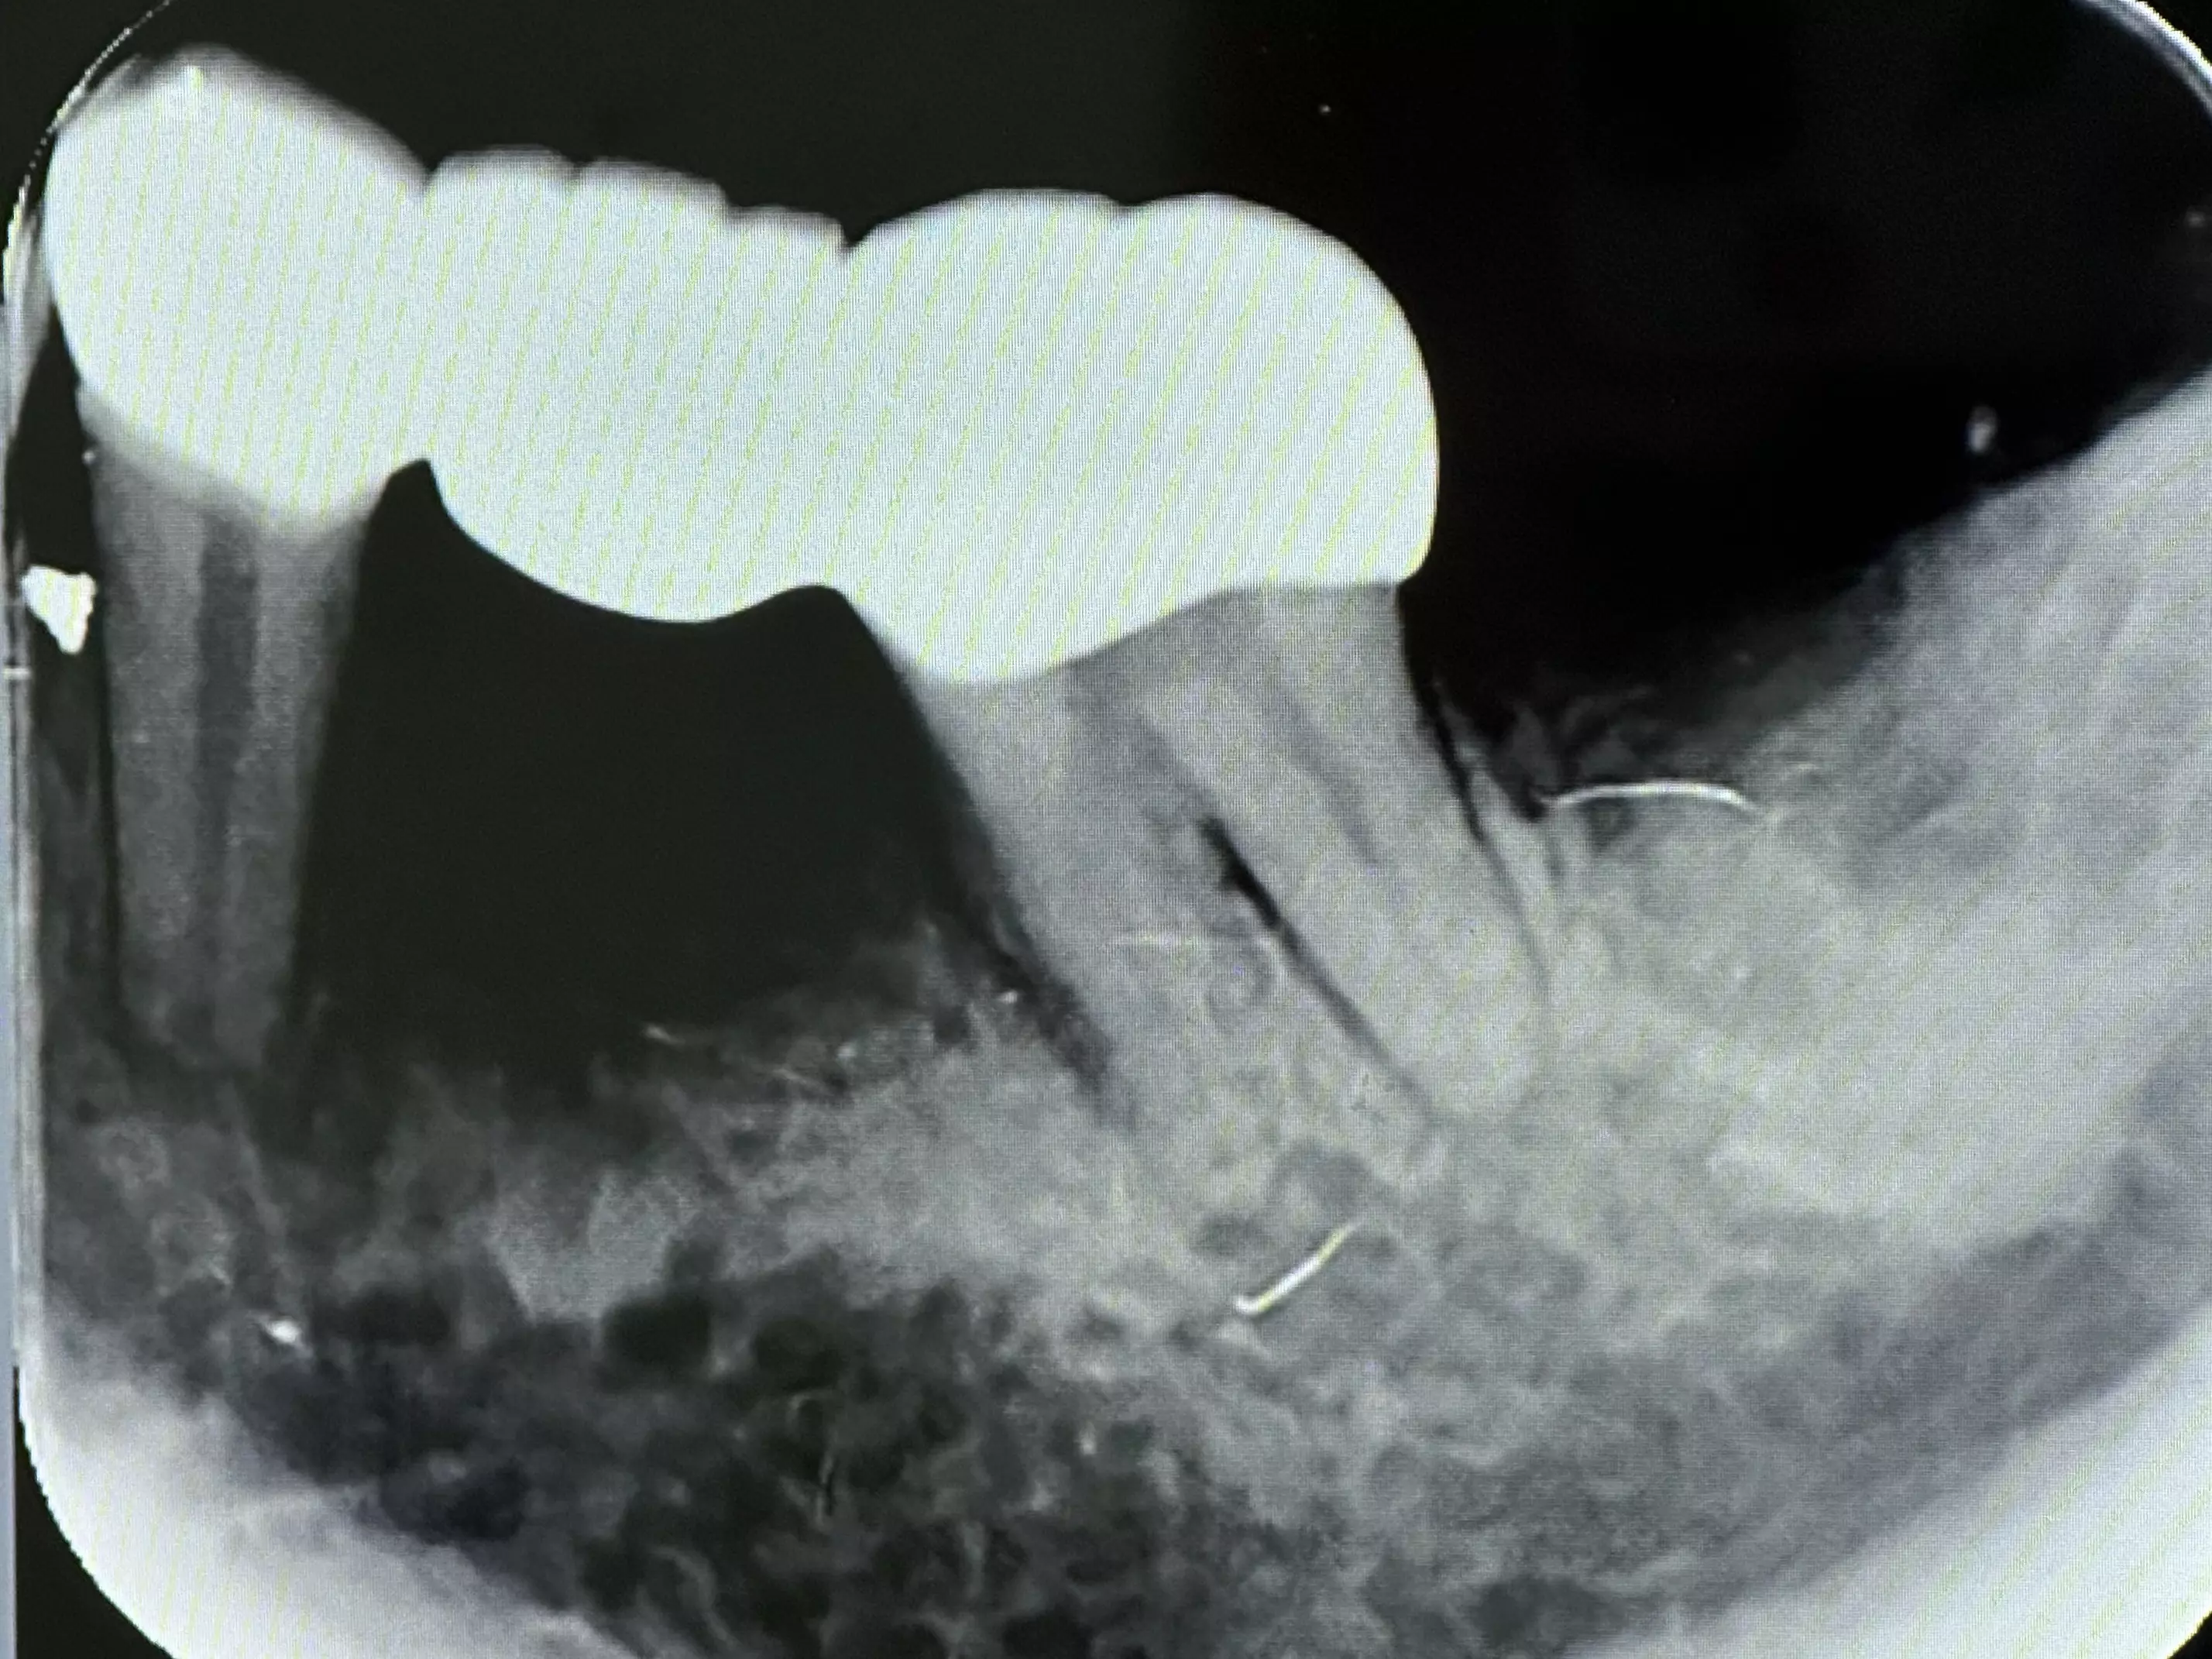

下方是患者初診的照片。患者有嚴重的咬合不正,但是基於身體條件,不適合進行齒顎矯正。下顎左側的缺牙使得她原本就不好的咬合功能變得雪上加霜,吃東西變得更困難。

下方是治療完成的照片。歷時四個多月,在患者、家屬、及醫療團隊的共同努力下,終於完成新的假牙製作。